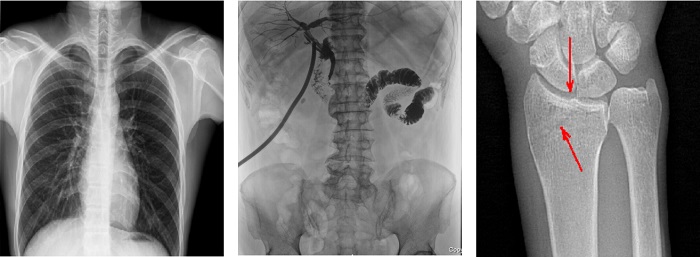

搭載100μm高品質(zhì)動(dòng)態(tài)平板探測(cè)器的普利德多功能懸吊動(dòng)態(tài)DR,不僅滿足常規(guī)的數(shù)字化X線全身攝影需求,同時(shí)還擁有數(shù)字?jǐn)z影、數(shù)字透視、數(shù)字造影、全景拼接等多種功能,極大地拓展了X線檢查在臨床應(yīng)用范圍,為醫(yī)院臨床應(yīng)用帶來更多實(shí)用價(jià)值?;诎傥⑵桨宓母咔宄上?,圖像清晰度與分辨率更高,可滿足不同檢查部位對(duì)細(xì)節(jié)成像的高品質(zhì)要求,在胸腹部、脊柱等復(fù)雜骨骼和軟組織的攝片上應(yīng)用,更便于觀察隱匿性病灶,精準(zhǔn)識(shí)別疑難病癥。

不同于靜態(tài)DR拍攝隱匿性病灶時(shí),由于組織重疊病灶難辨,耗費(fèi)時(shí)間更長(zhǎng)且易漏診、誤診,普利德多功能懸吊動(dòng)態(tài)DR可通過動(dòng)態(tài)實(shí)時(shí)連續(xù)成像,對(duì)于重疊部位病灶或者易被遮擋的病灶進(jìn)行多角度動(dòng)態(tài)觀察,毫秒級(jí)時(shí)間內(nèi)實(shí)現(xiàn)動(dòng)靜態(tài)轉(zhuǎn)換點(diǎn)片,快速、精準(zhǔn)完成攝片。比如隱匿性肋骨骨折,可在透視下觀察患者的呼、吸過程,避開重疊影像,快速點(diǎn)片,保證檢查部位的病癥不被遺漏,實(shí)現(xiàn)精準(zhǔn)診斷。